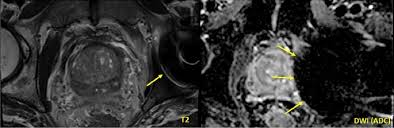

Imaging Diagnosis And Follow Up Of Advanced Prostate Cancer Clinical Perspectives And State Of The Art Radiology

Imaging Diagnosis And Follow Up Of Advanced Prostate Cancer Clinical Perspectives And State Of The Art Radiology from pubs.rsna.org